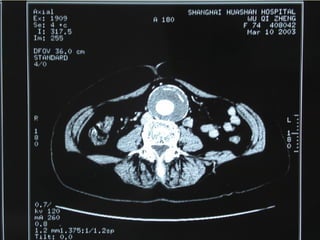

VR MPR MIP

 CT

10/20/15山血管外科网华 www.vascularcenter.cn 80

10/20/15山血管外科网华 www.vascularcenter.cn 81

10/20/15山血管外科网华 www.vascularcenter.cn 82

10/20/15山血管外科网华 www.vascularcenter.cn 84